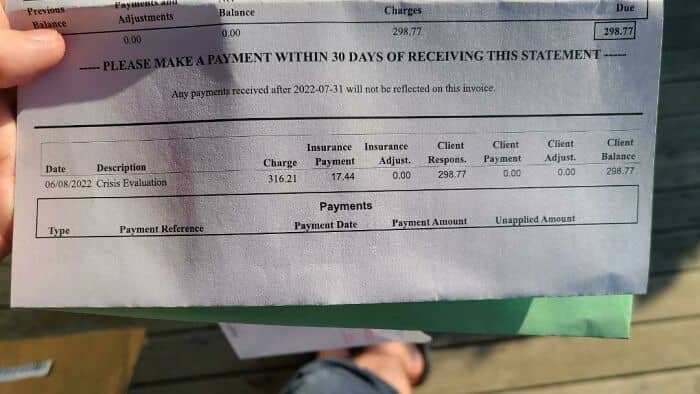

#50 Called A Local Mental Health Organization For Help After An Unaliving Attempt. This Isn’t Even The Hospital Bill

#51 No Longer An “Annual Exam” But “Preventative Annual Exam” So If I’m Not Perfectly Healthy With No Complaints I’ll Get Double Billed. Why Is It Like This?